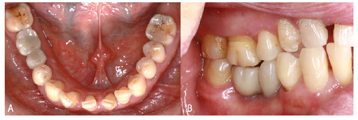

口内检查:45、46牙缺失,缺牙间隙近远中向18 mm,颊舌向9 mm,

龈距6~7 mm,对

牙略伸长,邻牙无倾斜;前牙散在间隙;张口度正常,颞下颌关节无弹响、无疼痛;缺牙区角化龈充足(图1)。

面照;B:颊面照

面照;B:颊面照CBCT检查:45牙缺牙区牙槽嵴顶宽度4.30 mm,高度17.63 mm;46牙缺牙区牙槽嵴顶宽度5.26 mm,高度16.20 mm(图2)。